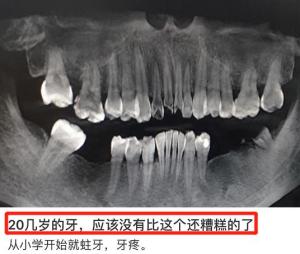

有一种病,是很多人童年的噩梦、成年的烦恼、老年的劲敌,那就是牙病。口腔疾病被世界卫生组织列为三大慢性病之一,它不仅容易贯穿一生,恶化程度还是不可逆的。如果得不到及时有效的治疗,蛀牙、轻度牙周炎会慢慢发展成牙根坏死、牙齿松动掉落。

世上最痛苦的莫过于,一颗牙已经没了,牙病却没有停止,反而牙齿越掉越多,甚至还有人年纪轻轻大牙都没了。